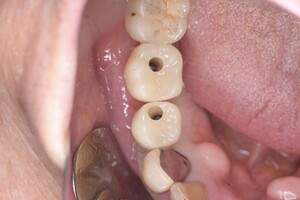

インプラント治療の症例4

レントゲン写真

- Befor

- After

口腔内写真

| 年齢 | 50代・男性 |

|---|---|

| 主訴 | 部位:左下6番7番 主訴:左下奥歯腫れて痛い。 |

| 治療内容 | 左下6番抜歯、左下6番7番骨造成、インプラント埋入 |

| 治療費 | 合計:1,232,000円 ・内訳 診断料:55,000円 サージカルガイド2本:66,000円 GBR:110,000円×2本 埋入料:165,000円×2本 静脈内鎮静麻酔:77,000円 2次OPE:22,000円×2本 仮歯:55,000円×2本 上部構造(フルジルコニア):165,000円×2本 (2023年1月現在) |

| 治療期間 | 約8ヶ月 |

| リスク・副作用 | リスク・副作用 |

| 治療方針 | 元々支台歯に負荷がかかりやすいとされている延長ブリッジを抜歯し、1本単体でしっかりかめるようにインプラントを2本埋入した。骨吸収も進んでいたため、※GBR法で骨造成を同時に行った。 治療と並行して、全顎的な歯周病治療も行い、今後は歯周病が進行しないよう、こまめにメンテナンスに通っていただく。 |

| 特記事項 | ※1 GBR・・・骨再生誘導法。骨の高さや厚みを人工骨や人工膜などを使用し再生する方法 |

| 担当者所見 | 6番は歯根分割された被せ物が7番の欠損部との延長ブリッジとされており、強い咬合と歯周病も相まって負荷がかかり動揺し、歯として機能しなくなったため、抜歯となった。 |